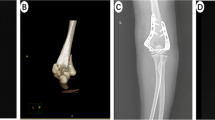

Through imaging examinations such as X-ray and CT, it is determined whether there is a medial cortical bone defect. For patients with medial cortical bone defects (such as comminution of the medial column and discontinuity in the Calcar region) or those with a varus tendency of the humeral head (the head-shaft angleā<ā120°) after reduction, a humeral calcar screw is inserted. Before the operation, the bone condition in the Calcar area, the type of fracture, the degree of displacement, etc., were precisely measured to determine the appropriate length, diameter, and implantation angle of the Calcar screws (Fig.Ā 2).

Radiographic measurements of a representative patient. (a) The humeral head height (HHH) was defined as the distance between uppermost edge of the plate and the uppermost part of the humeral head; (b) The humeral neck-shaft angle (NSA) was defined as the angle between a line that is perpendicular to the articular segment or atomic neck of the humerus and a line that bisects the humeral shaft; (c) Tip distance is defined as the distance from the calcar screw to the articular surface of the humeral head. (d) The calcar distance refers to the distance from the calcar screw to the calcar.